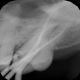

Diagnostyka radiologiczna jest jednym z podstawowych badań poprzedzającym właściwe leczenie pacjentów stomatologicznych. Zdjęcia RTG które wykonujemy w naszych gabinetach, pozwalają ocenić stan zęba, korzeni, tkanek, a także kości. Dokładne rozpoznanie może ułatwiać ułożenie indywidualnego planu leczenia i tym samym zwiększać szanse na skuteczną terapię. Pacjentom odwiedzającym nasze gabinety stomatologiczne proponujemy wykonanie zdjęcia zębów dla ortodonty, do leczenia kanałowego oraz pantograficzne, ukazujące żuchwę, stawy skroniowo-żuchwowe, a także zatoki szczękowe.

Nasze przykładowe realizacje :